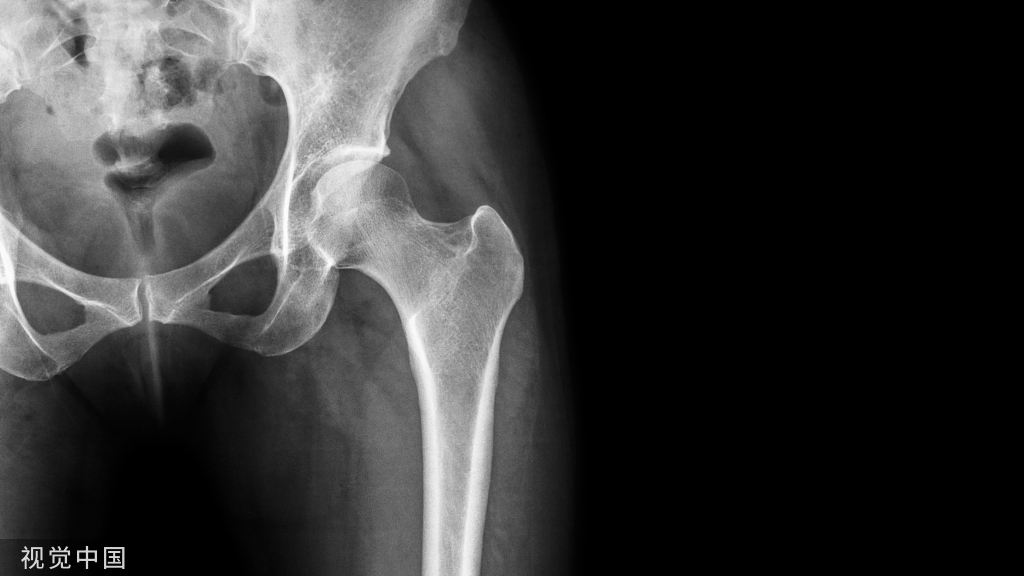

3.髋关节前外侧1)病人仰卧,在患髋后方垫一沙袋,使髋部高于手术台面。

2)患侧髋下垫一双层中单,遮盖健侧下肢及手术台尾部,中单上缘自大腿根部拉向上、中部和对策,遮盖会阴前面。

3)沿臀下铺第1块治疗巾,自大腿根部内侧经会阴铺第2块治疗巾,自髂前上棘至臀后铺第3块治疗巾,自臀后外侧至髂骨后铺第4块治疗巾,钳子固定四角。

4)术者用中单,拖住助手放下的下肢,放于手术台上,自脚至大腿中段进行包裹,绷带包扎。5)贴手术巾,套铺大孔被,收紧洞口,钳子固定。